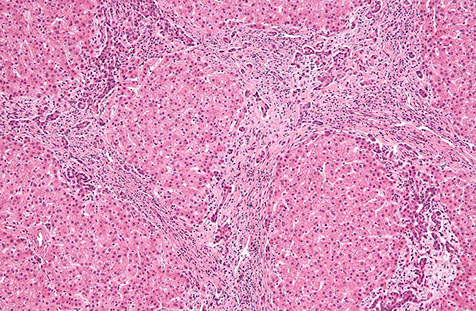

Micro: hepatic parenchyma with diffuse nodularity from small atrophic hepatocytes in zone 3, with normal to slightly big zone 1 and 2 hepatocytes, which is highlighted c reticulin stain

- may have portal vascular changes (hepatoportal sclerosis or portal vein wall hypertrophy)

• Hepatocellular nodules without fibrosis

– Hepatocytes between nodules are small, flattened, 2 cells thick

– Reticulin network compressed between nodules

IHC: No fibrosis on Masson trichrome

nodular regenerative hyperplasia with regenerative nodule (white arrow) bordered by irregular aligned small-sized hepatic trabeculae (black arrows)

nodular appearance of liver parenchyma (white arrows) characteristic of nodular regenerative hyperplasia. Areas with sinusoidal congestion are also present (black arrow